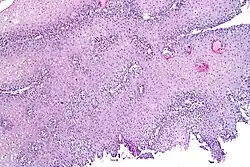

Nerve endings and acid-sensitive ion channels in the deepest layer of the esophagus are usually protected by anatomical barriers. However, in gastroesophageal reflux disease (GERD), one of the earliest signs of damage is the development of dilated intercellular spaces (DISs) in the esophageal lining. These spaces weaken the protective barrier, allowing acid and other substances to seep in.[13][11] This triggers pain-sensitive nerves, which send signals to the brain and cause the sensation of heartburn.[11][14]

Diagnostic investigations for the evaluation of heartburn include endoscopy and esophageal pH monitoring. GERD is commonly diagnosed based on symptoms of heartburn or regurgitation. Endoscopy may be used to evaluate people who do not respond to treatment for heartburn or those with alarm symptoms such as persistent vomiting, gastrointestinal bleeding, iron-deficiency anemia, involuntary weight loss, difficult/painful swallowing (dysphagia, odynophagia), epigastric mass, family history of esophageal or gastric cancer, and new onset of symptoms in those older than 50 years of age.[23]

Endoscopy is a method used to detect abnormalities in the esophageal lining such as erosive esophagitis and Barrett's esophagus. Biopsies taken during an endoscopy can help assess for other conditions linked to heartburn, such as eosinophilic and lymphocytic esophagitis.[14] The esophageal 24-hour pH test or the multichannel intraluminal impedance-pH test is often performed in those with refractory heartburn who have undergone an endoscopy. High-resolution esophageal manometry (HREM) is the standard test for diagnosing esophageal motor disorders. It helps rule out major motility issues in those with persistent heartburn who have normal endoscopy and pH testing. Motility disorders include achalasia, esophagogastric junction outflow obstruction, diffuse esophageal spasm, jackhammer esophagus, and absent contractility. HREM can also distinguish GERD from conditions like rumination and supra-gastric belching. In some cases, gastric scintigraphy may be used to detect gastroparesis.[24]